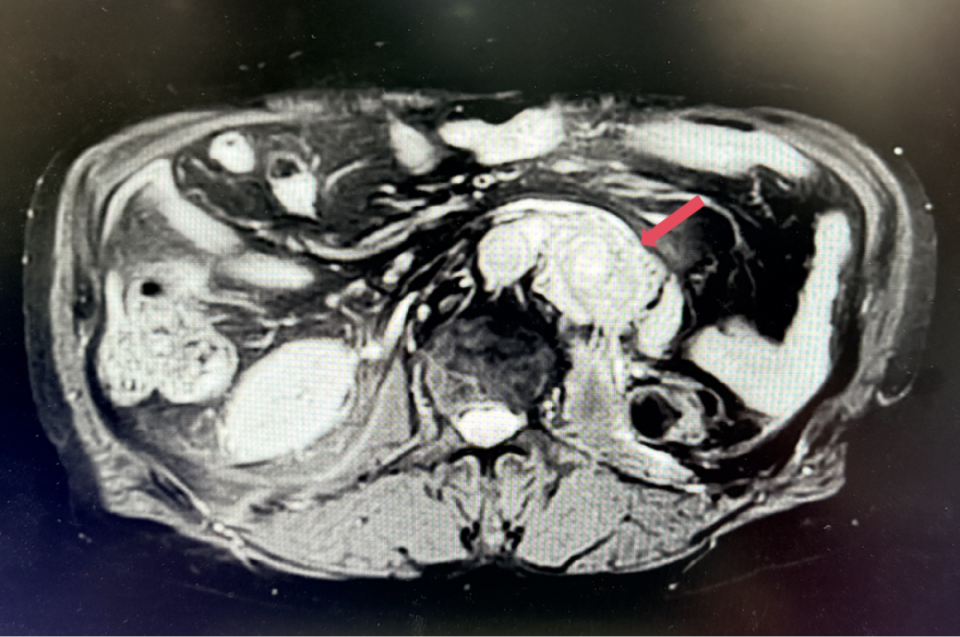

2023年11月:治疗10个月(C15)评估,肿瘤负荷减少至41mm,维持PR。

2023年11月,最深应答